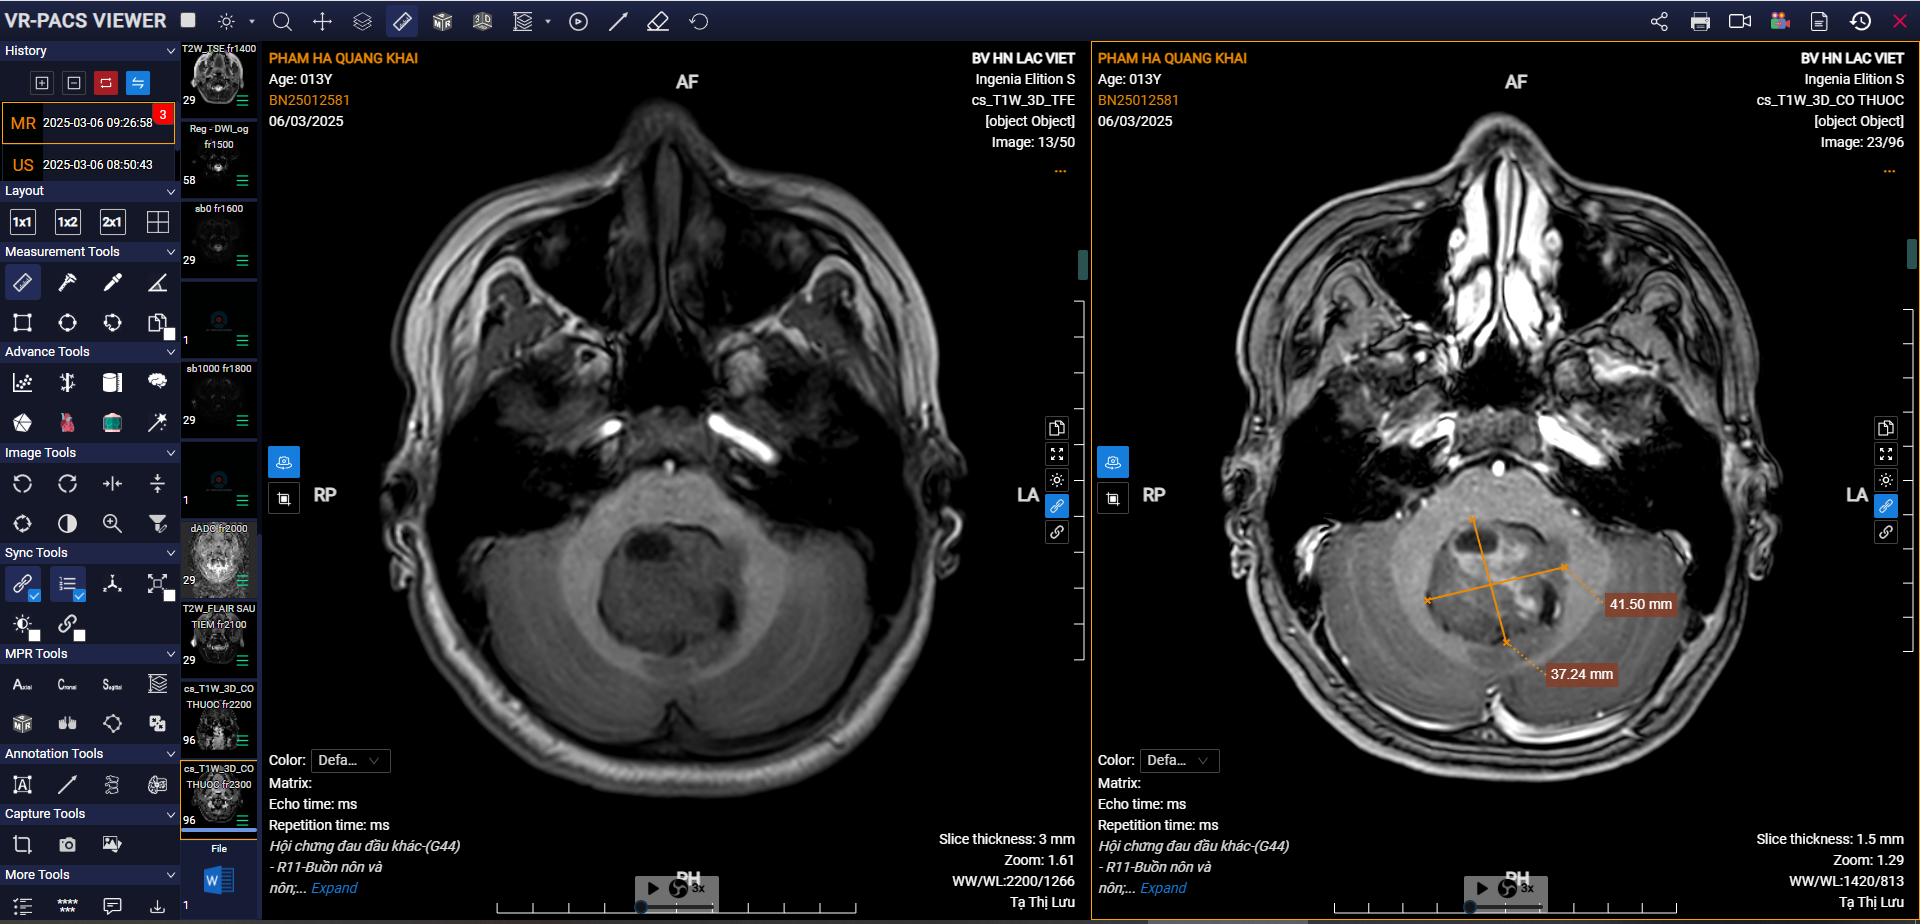

7. Ca bệnh thực tế: Phát hiện u não ở trẻ 14 tuổi nhờ MRI 3.0 Tesla

Một bệnh nhi 14 tuổi đến khám Tại Bệnh viện Hữu Nghị Lạc Việt vì đau đầu kéo dài, buồn nôn và mệt mỏi nhiều tuần. Bác sĩ chỉ định chụp MRI não 3.0 Tesla để tầm soát.

Kết quả cho thấy:

Khối u trong não thất IV

Lan vào lỗ Luschka bên trái

Dấu hiệu giãn nhẹ não thất phía trên

Nhờ phát hiện sớm, bệnh nhân đã tránh được nguy cơ tăng áp lực nội sọ, nôn vọt, rối loạn vận động.